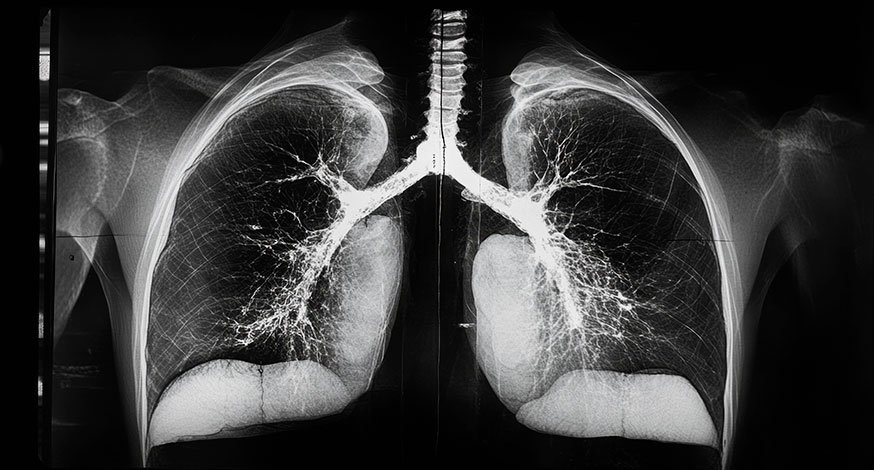

En el estudio realizado es fundamental el TAC, ya que, si existe una imagen radiológica compatible, sin reconocer otra causa, puede ser suficiente para el diagnóstico. En algunos casos será necesario la valoración en un comité multidisciplinar para plantear la necesidad de biopsia quirúrgica pulmonar.